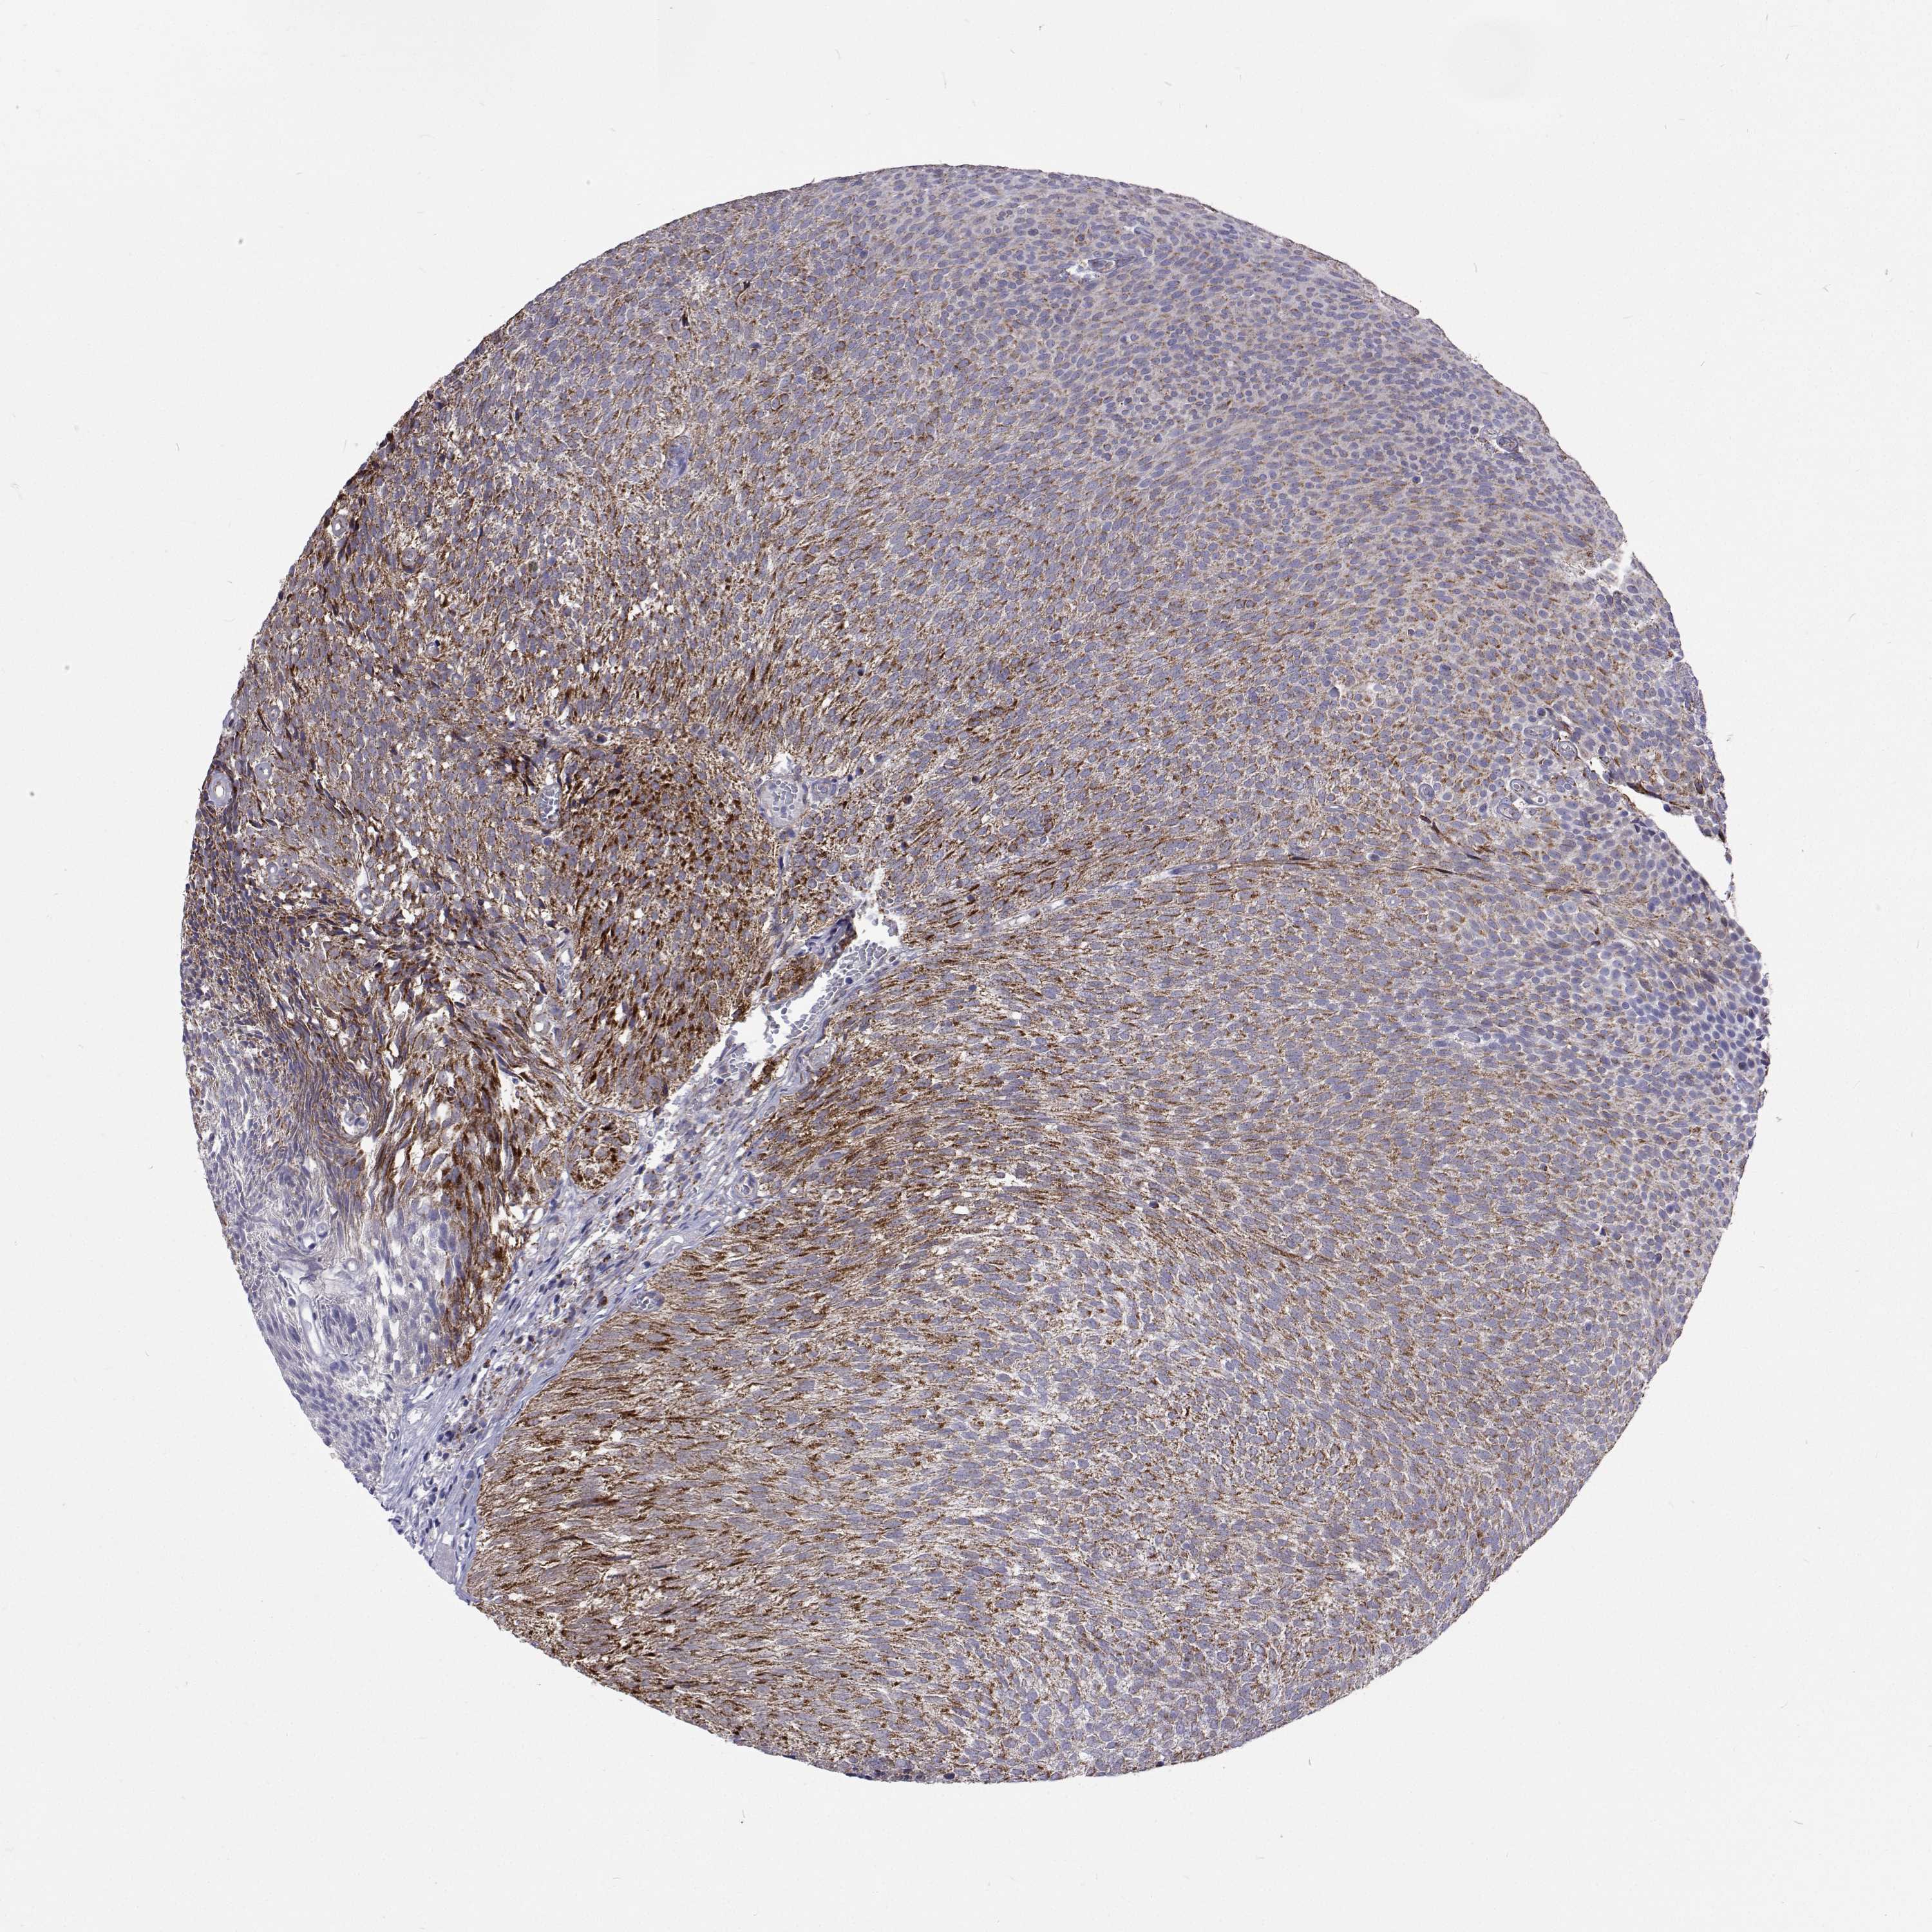

UROTHELIAL CANCER - Protein expressioni

A mouse-over function shows sample information and annotation data. Click on an image to view it in a full screen mode. Samples can be filtered based on level of antibody staining by selecting one or several of the following categories: high, medium, low and not detected. The assay and annotation is described here.

Note that samples used for immunohistochemistry by the Human Protein Atlas do not correspond to samples in the TCGA dataset.

Antibody stainingi

Antibody staining in the annotated cell types in the current human tissue is reported as not detected, low, medium, or high, based on conventional immunohistochemistry profiling in selected tissues. This score is based on the combination of the staining intensity and fraction of stained cells.

Each image is clickable and will lead to virtual microscopy that enables deeper exploration of all samples and also displays staining intensity scores, fraction scores and subcellular localization as well as patient and tissue information for each sample.

Antibody HPA038300

Antibody HPA038301

Antibody HPA061546

Staining

High

Medium

Low

Not detected

Intensity

Strong

Moderate

Weak

Negative

Quantity

>75%

75%-25%

<25%

None

Location

Nuclear

Cytoplasmic/membranous

Cytoplasmic/membranous,nuclear

Urothelial carcinoma, High grade

Urothelial carcinoma, Low grade

Urothelial carcinoma, NOS